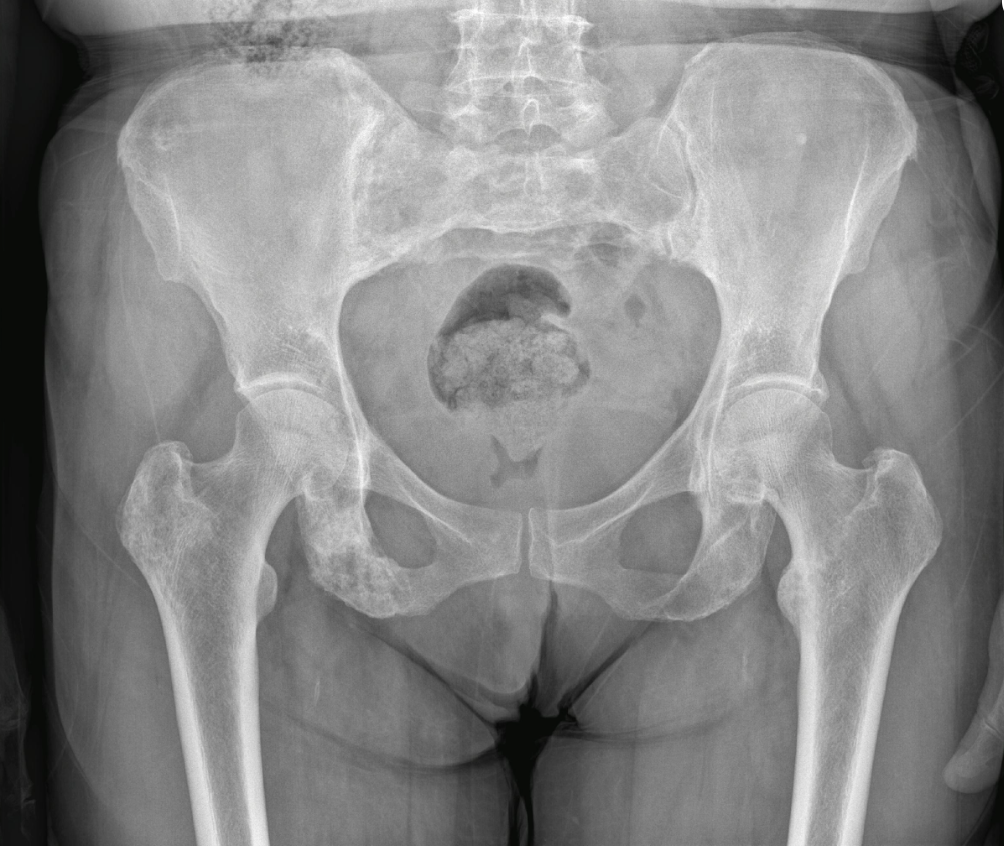

Raio_X_DIU

Radiografia de abdome (perfil). Observa-se dispositivo intrauterino (DIU) projetado fora da topografia uterina, localizado na cavidade abdominal, compatível com perfuração uterina e migração do dispositivo. Achado raro, porém relevante, com potencial risco de complicações.